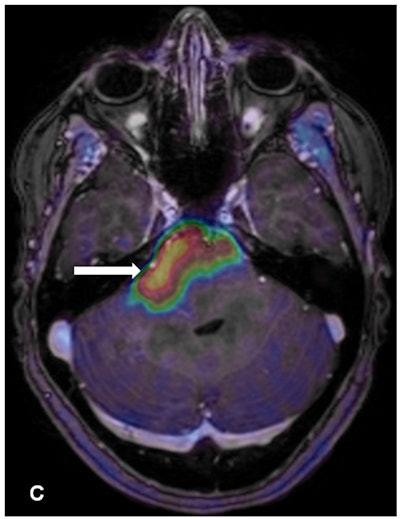

Contrast enhancement from the PET radiotracer FET highlights the brainstem glioma. Image courtesy of Albatly et al and the Journal of Nuclear Medicine.Burger cited a few limitations of the study, including the small patient sample. The results have to be "taken with care, the Kaplan-Meier analysis especially in such a small cohort," she said.